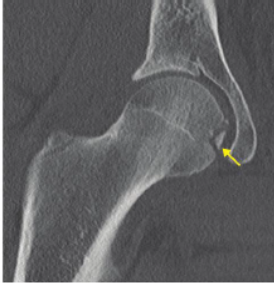

Clasificacion de pipkin

Tipo 1: luxacion de cadera + fractura de cabeza del fémur DEBAJO de la fóvea (zona de

carga)

Tratamiento de pipkin 1 (fractura cabeza femoral)

Reduccion adecuada —> conservador

Inadecuada —> RAFI con tornillos subarticulares

Tipo 2 —> luxación de cadera + fractura de cabeza del fémur ENCIMA de la fóvea

Afectan la superficie de carga→ practicamente TODA la cabeza del femur